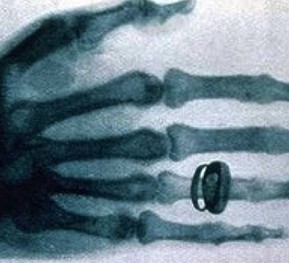

X光機主要是由X光機電源,X光球管以及控制電路等組成,是產生X光的設備,目前已廣泛應用于醫(yī)院協(xié)助醫(yī)生診斷疾病,工業(yè)的無損探傷,科學教育,機場和火車站的安全檢查等

圖像監(jiān)控法是直接從x射線透視圖像構形來判斷物品的,因此,被檢物是否可疑,取決于監(jiān)視器或顯示器上的圖像。顯示器或監(jiān)視器上出現(xiàn)的不常見物或異形物,都應視為可疑物品。那些不能準確辨認的物品也應視為可疑物品,需仔細觀察,根據需要可將圖像定位分析。